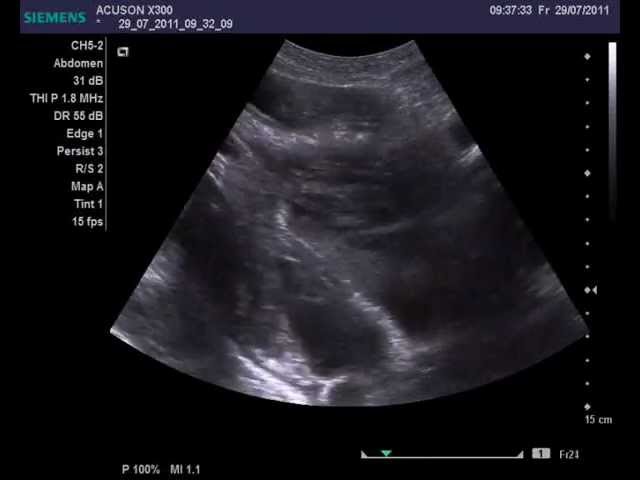

- УЗИ (ультразвуковое исследование) плевральной полости.

- Диагностическая пункция – извлечение жидкости из полости плевры (полость, образованная листками плевры – наружной оболочки легких) путем ее прокола специальной иглой с последующим лабораторным исследованием полученной жидкости.